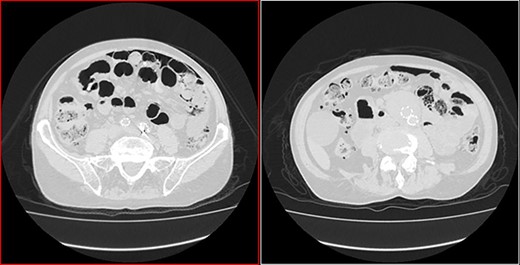

He arrived at the emergency department walking and with no clinical distress. He was complaining of hematuria for a month and worsening of chronic constipation in the last 2 days. Physical examination demonstrated discrete abdominal distention. Laboratory tests showed normal c-reactive protein (CRP), white blood cell count and lactate level. A new CT revealed no change in the previous findings: intestinal pneumatosis and pneumoperitoneum (Figs 2 and 3).

Coronal CT image in lung window showing pneumoperitoneum and ‘bubbles’ within the walls of small intestine and in the mesentery.